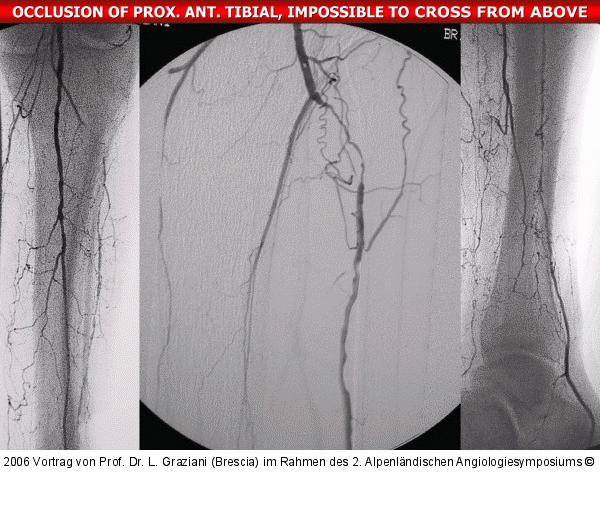

Vortrag von Prof. Dr. L. Graziani (Brescia) im Rahmen des 2. Alpenländischen Angiologiesymposiums

PTA of the foot arteries in diabetics: Extremities Extreme Angioplasty

Abbildung 69: P.O.B.A.